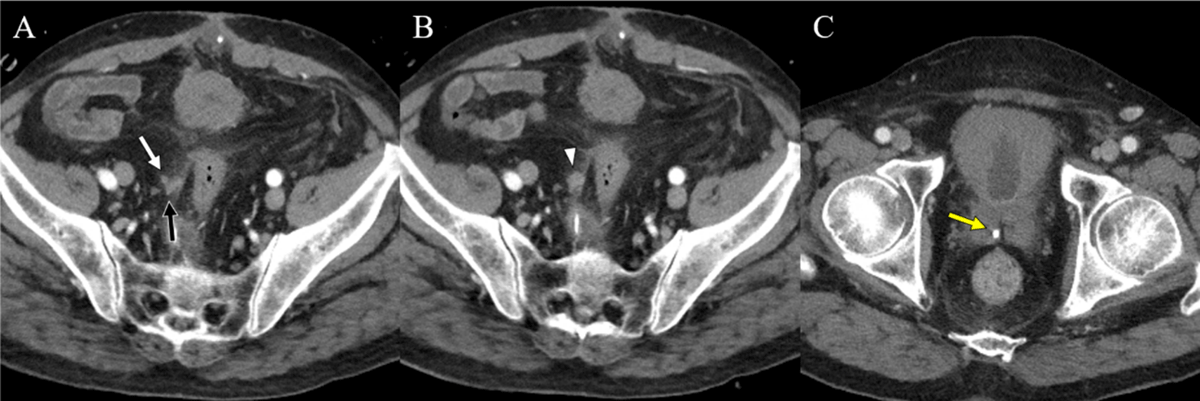

Figure 2

Follow-up CT images were taken after 11days. Axial images (A, B) show no abscess other than enhancing soft tissue (arrowhead) around the defect site of the VD wall. An axial image (C) shows a remnant stone at the distal VD. (white arrow: proximal VD, black arrow: distal VD, yellow arrow: VD stone).